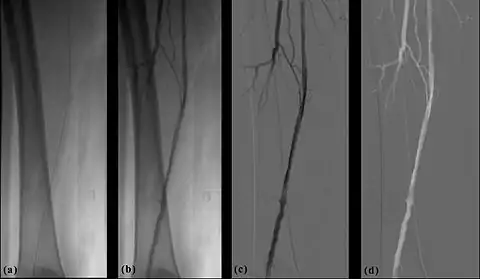

- The temporal-averaging feature of digital noise reduction can also be used for image presentation purposes so that the time course of the movement of contrast medium during a study can be displayed using just one image - see an example in Figure 7.4 from the peripheral study shown above - instead of a sequence of numerous images. Such an image is sometimes referred to as a Vascular Trace.

- One method of temporal filtration, referred to as Integrated Mask-Mode DSA involves adding (also called integrating) a number of images, acquired prior to the arrival of the contrast medium, to form an integrated mask image and adding a number of peak-opacification images to form an integrated live image. This is the process that was used to generate the vascular trace image in Figure 7.4. Thus, when four images are used to generate each integrated mask and live images, eight of the 25 images are now used in the subtraction process and, as a result, only 68% of the dose is wasted, and a subtraction image with lower noise results.